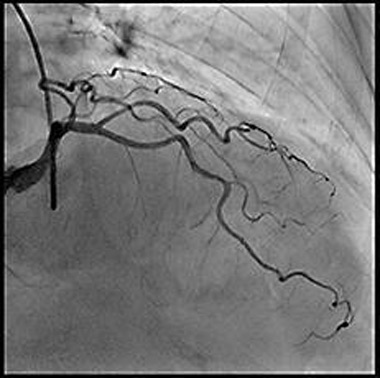

血管造影装置

血管造影装置は、カテーテル

(特別な管)を

血管に挿入して造影剤を流し、

血管の形態を動画や静止画として

描出する装置です。

循環器内科医はその画像を基に、狭くなった血管に対して小さな風船や金属の筒を用いて治療を行います。主に狭心症や心筋梗塞などの虚血性心疾患に対して治療する経皮的冠動脈形成術(PCI)や、末梢血管、腎動脈狭窄・閉塞に対して治療するEVT、不整脈に対して治療するアブレーション等に使用されます。